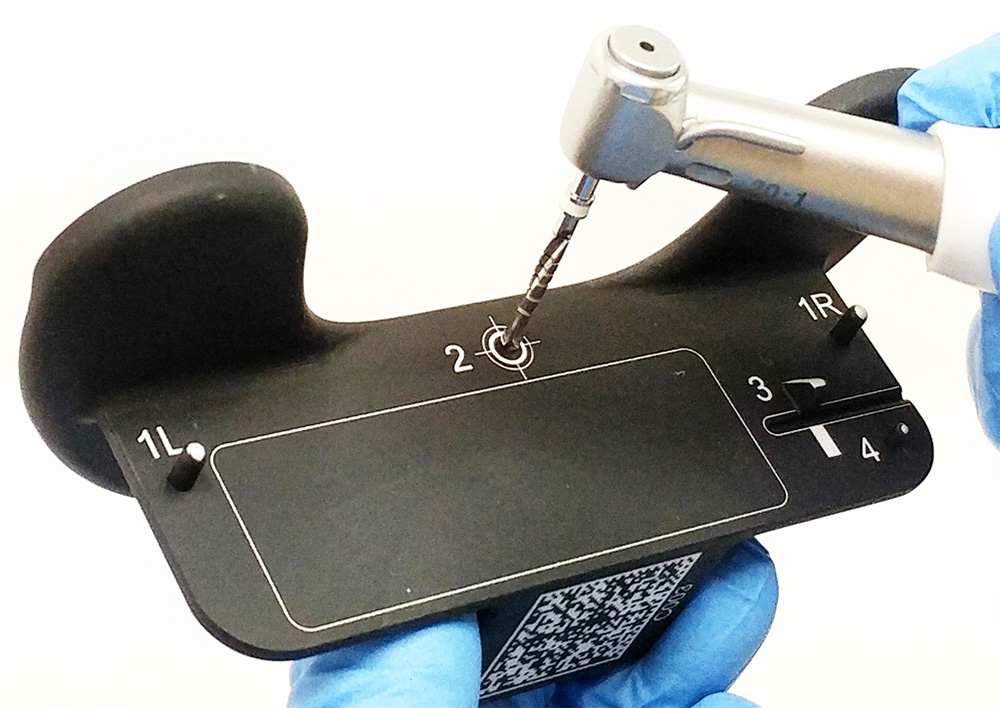

Browse our specialized Calibration In Dynamic Navigation Surgery In Implamt portfolio with numerous expertly curated photographs. optimized for both digital and print applications across multiple platforms. providing reliable visual resources for business and academic use. Each Calibration In Dynamic Navigation Surgery In Implamt image is carefully selected for superior visual impact and professional quality. Perfect for marketing materials, corporate presentations, advertising campaigns, and professional publications All Calibration In Dynamic Navigation Surgery In Implamt images are available in high resolution with professional-grade quality, optimized for both digital and print applications, and include comprehensive metadata for easy organization and usage. Our Calibration In Dynamic Navigation Surgery In Implamt collection provides reliable visual resources for business presentations and marketing materials. Whether for commercial projects or personal use, our Calibration In Dynamic Navigation Surgery In Implamt collection delivers consistent excellence. The Calibration In Dynamic Navigation Surgery In Implamt archive serves professionals, educators, and creatives across diverse industries. Regular updates keep the Calibration In Dynamic Navigation Surgery In Implamt collection current with contemporary trends and styles. Advanced search capabilities make finding the perfect Calibration In Dynamic Navigation Surgery In Implamt image effortless and efficient. Multiple resolution options ensure optimal performance across different platforms and applications.